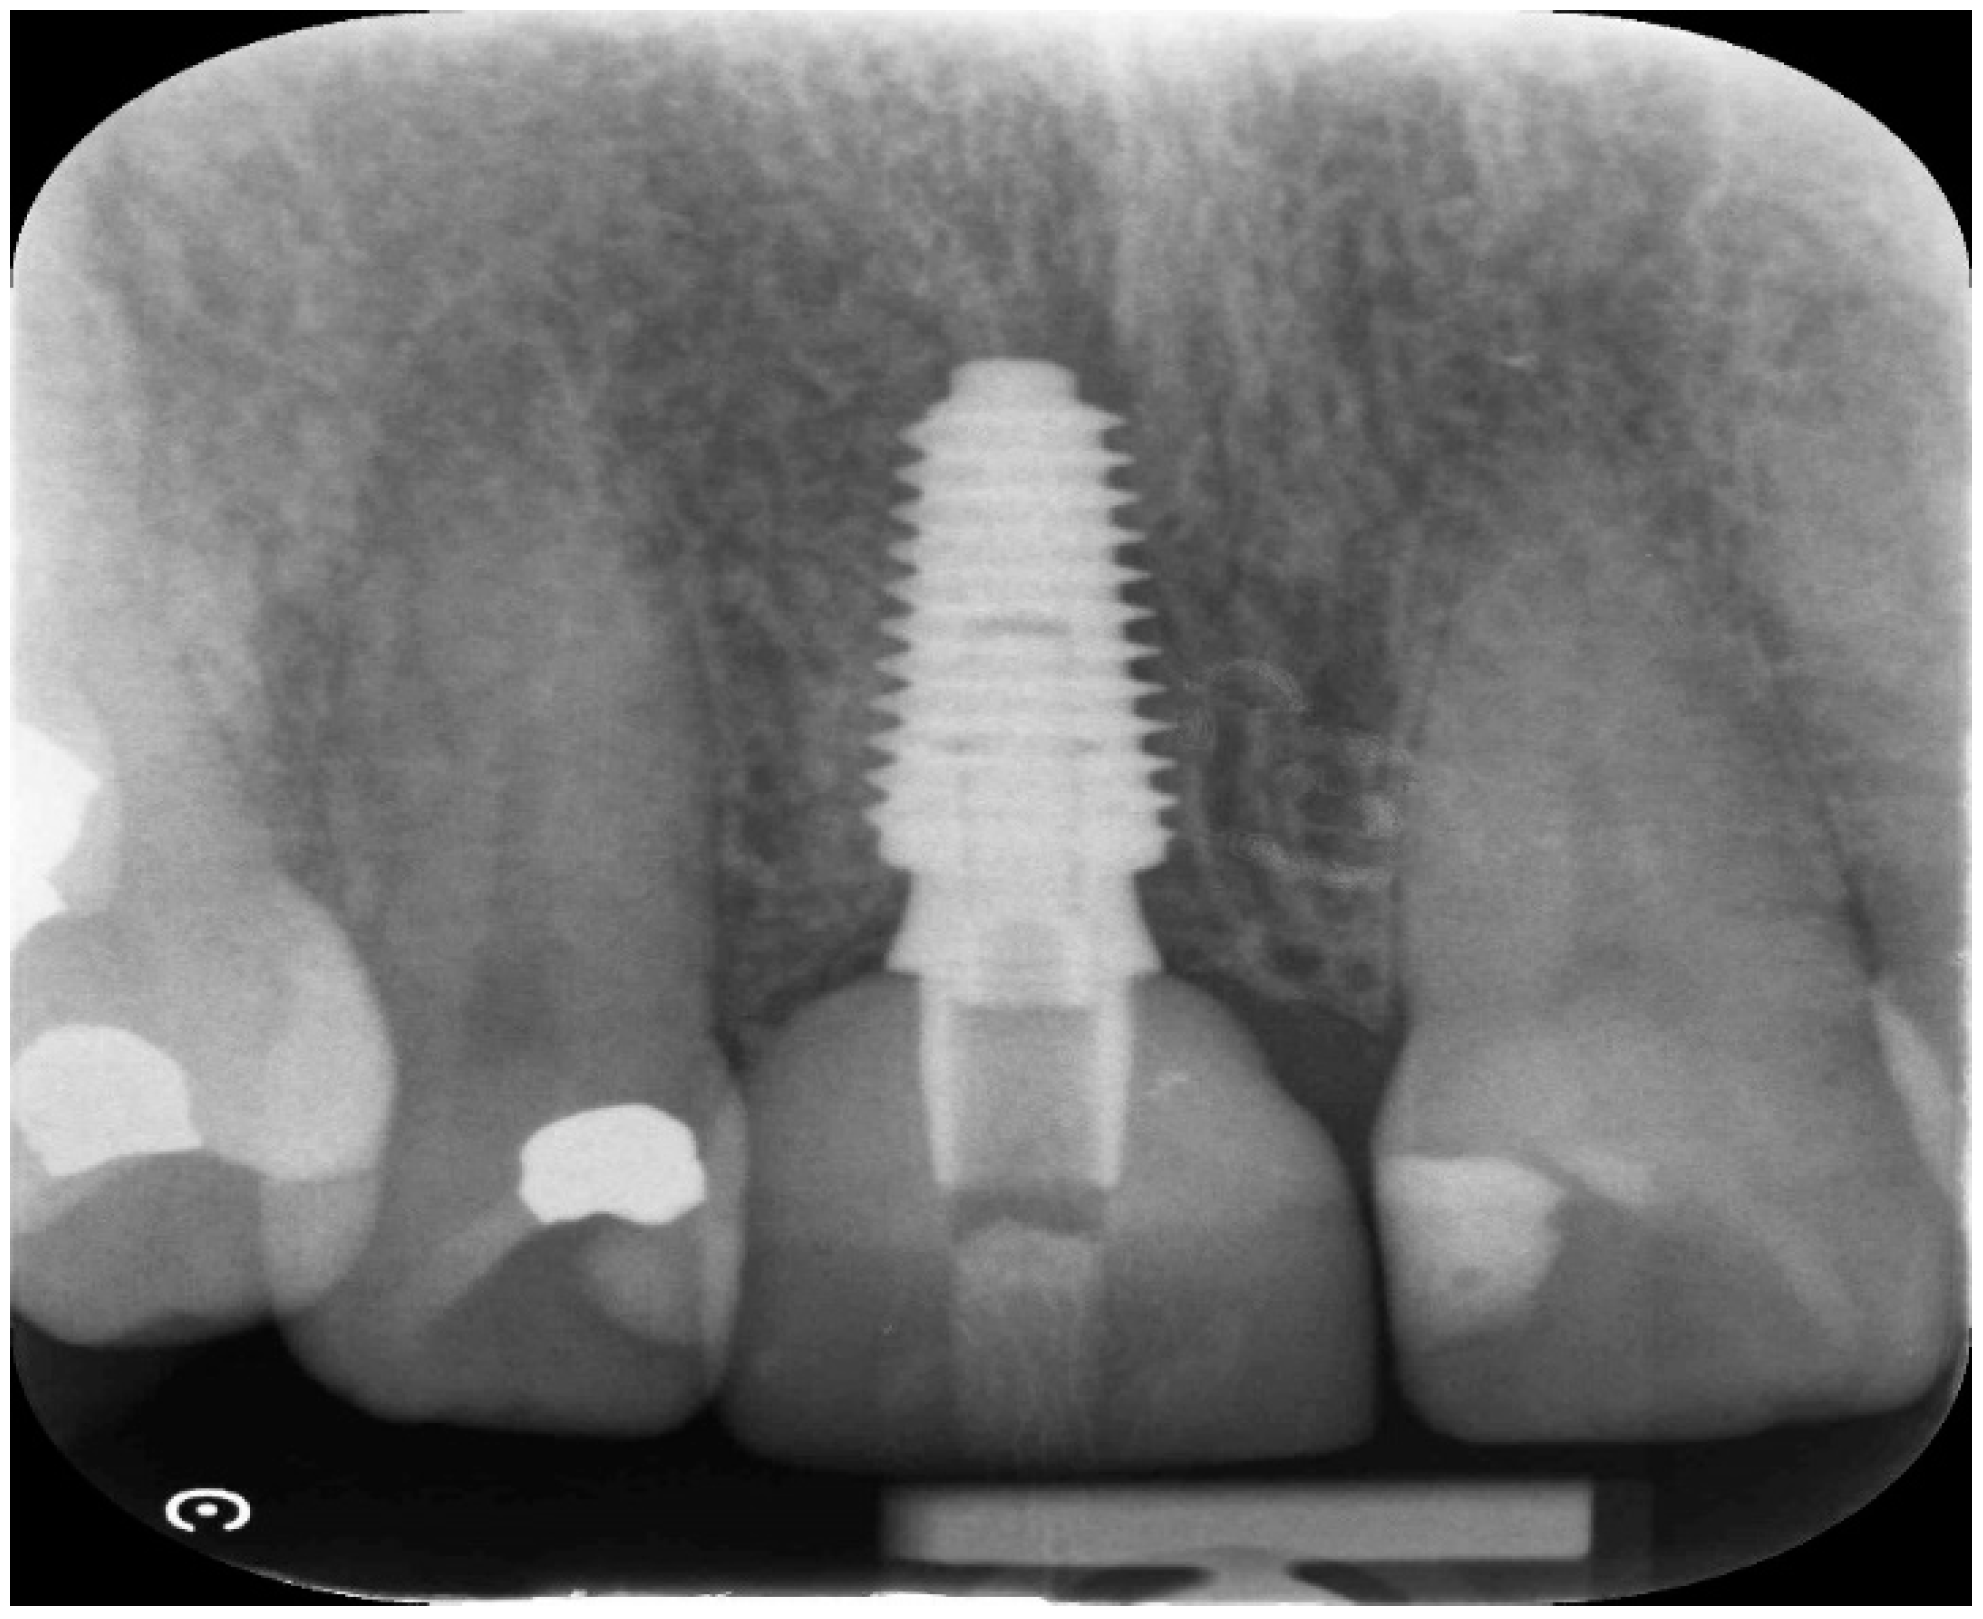

Case study 1

| Case 1 | open SA | Full contour | excellent | high | D2-3 | None | 8 weeks | 6 weeks | No crestal bone loss |